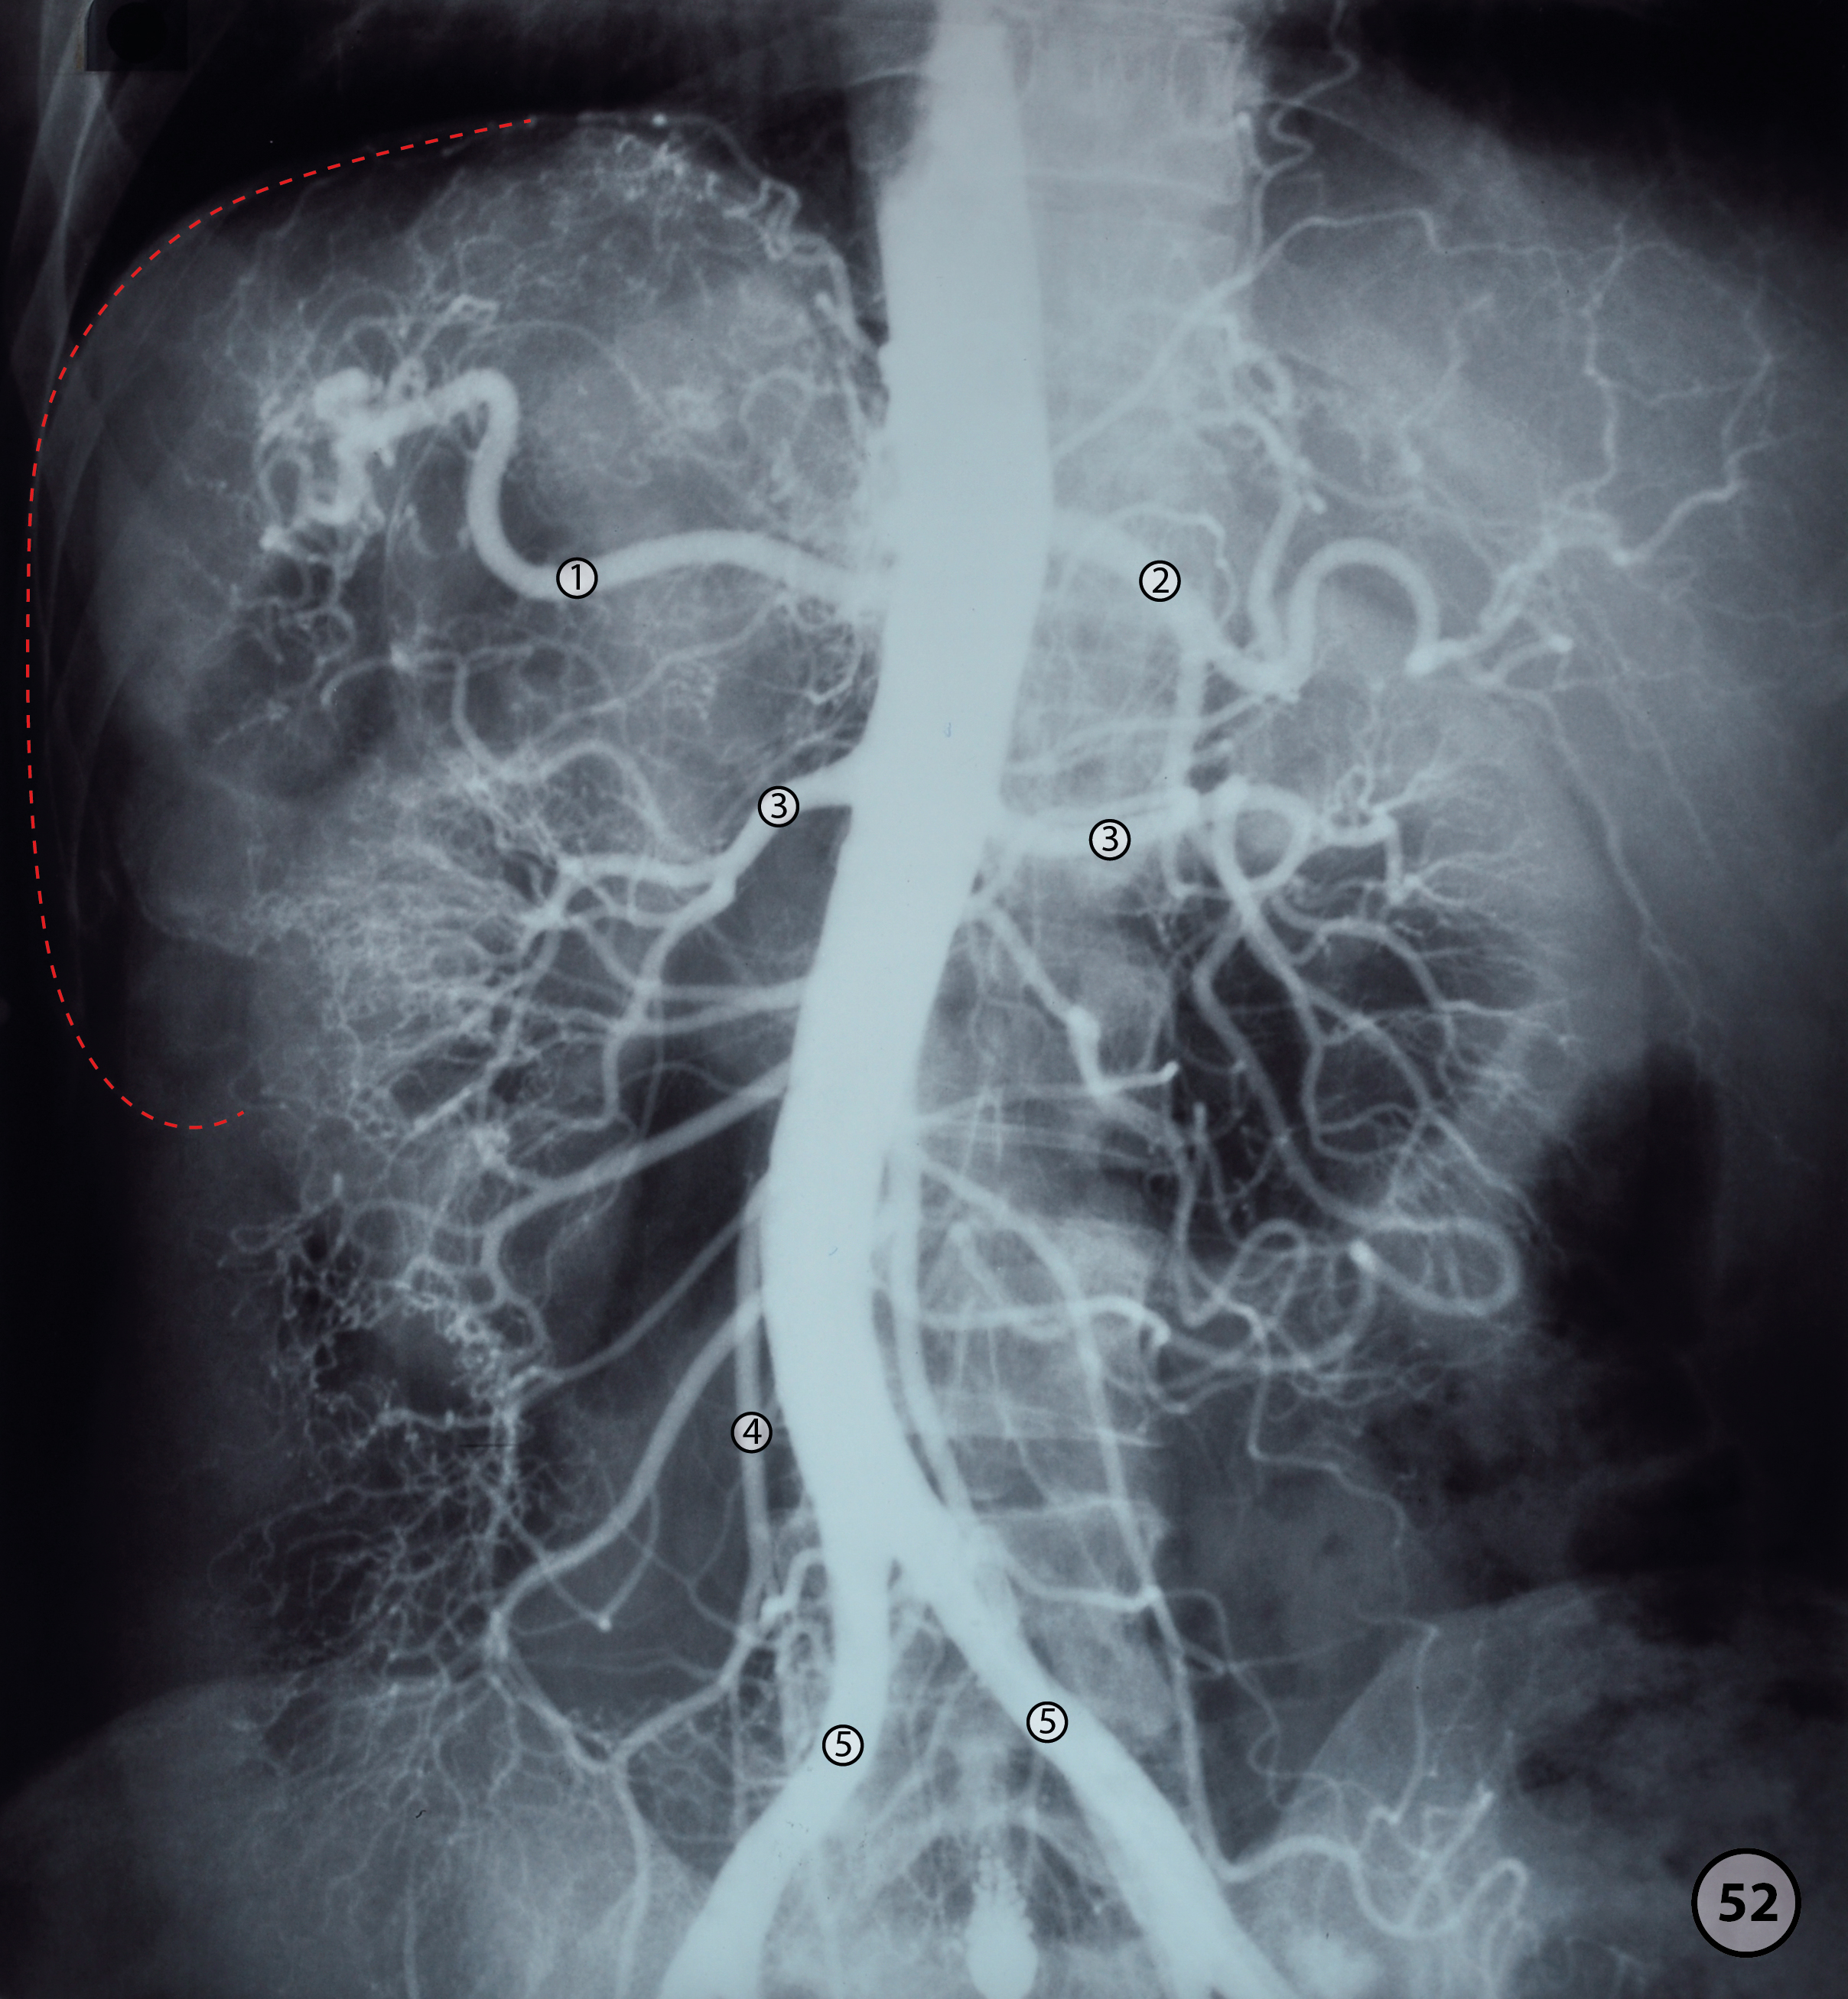

Anatomical structures in item:

Aorta abdominalis

Arteria gastrica dextra

Arteria hepatica

Arteria iliaca communis